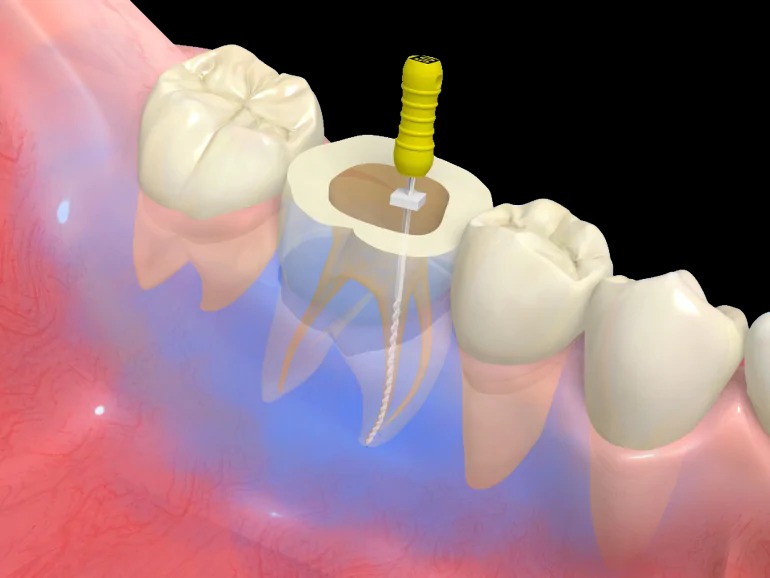

Ni-Tiファイル

従来はステンレス製のヤスリ状の物を用いていましたが、このファイルは柔らかく、曲がった根管などに対しても対応でき、治療時間の短縮にも繋がります。

4EMR

歯の根の長さを測ります。

5根管洗浄

内部の消毒を行います。一般的には次亜塩素酸水溶液を用います。当院では、より洗浄効果の高い次亜塩素酸水溶液とEDTA(根管内に詰まった切削片を溶かす)を交互に使い洗浄します。

6根管貼薬

根管内に水酸化カルシウム製剤を置きます。

さらに、根管内の細菌の現症を行って、症状が落ち着くのを待ちます。

7根管充填

症状があれば日にちを空けて充填します。

ゴムの様な材質で緊密に詰めていき、再度細菌が繁殖しないようにスペースを閉鎖します。

最後にレントゲンで確認します。